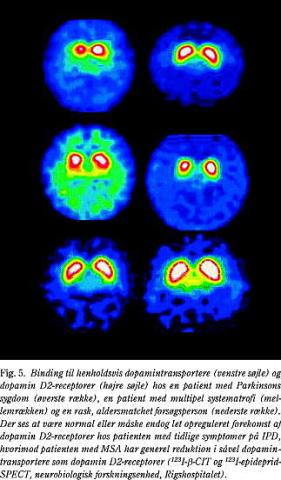

MSA, også kaldet Shy-Dragers syndrom, er en sygdom, der primært er karakteriseret ved rigiditet, ataksi og autonome forstyrrelser. Det er påvist, at omkring 10% af de patienter, der oprindeligt blev antaget at have IPD, ved neuropatologiske undersøgelser i stedet viste sig at have haft MSA. Eftersom ca. halvdelen af patienter med MSA udviser bedring under levodopa-behandling, kan manglende behandlingsrespons ikke anvendes som markør for diagnosen. Ved MSA findes reduceret D2/D3-binding hos omkring 63% (22) (Fig. 5), hvorimod 18 F-DOPA-PET synes at være mindre egnet til at skelne MSA fra IPD (23).